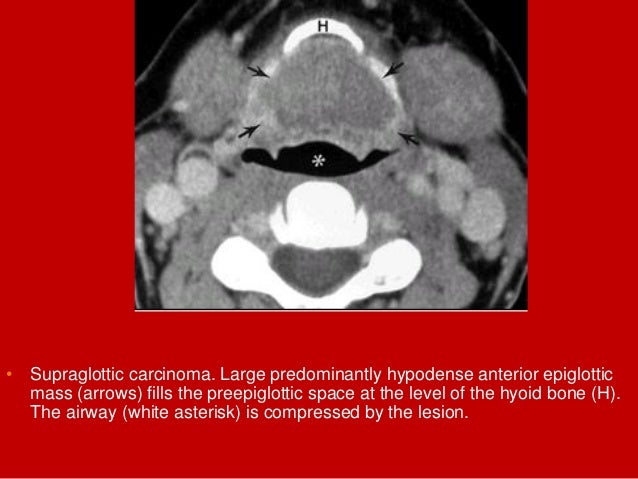

21. 21. • Supraglottic carcinoma. Large predominantly hypodense anterior epiglottic mass (arrows) fills the preepiglottic space at the level of the hyoid bone (H). The airway (white asterisk) is compressed by the lesion.